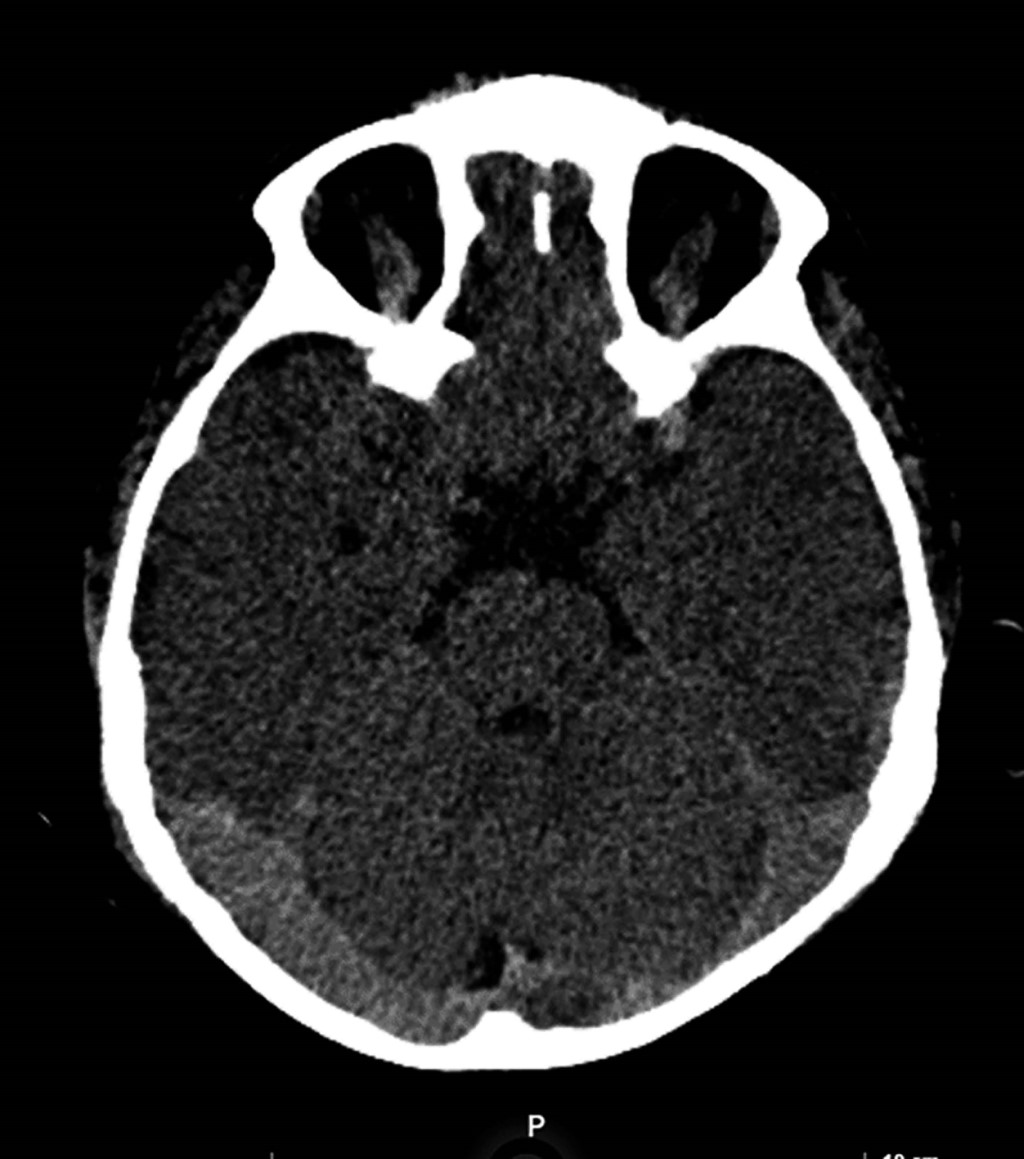

Tuvimos una defunción, correspondió a un varón de seis años, previamente sano, nueve días previos con cuadro gripal, dolor abdominal, vómito, fiebre no cuantificada. Posteriormente presentó hematemesis y epistaxis; al presentar alteración del estado de alerta acudió a nuestro hospital, ingresando con Glasgow de 10, dolor abdominal intenso. Sus resultados de laboratorio se expresan en la Tabla 5. En la tomografía pulmonar se aprecia derrame pleural (Figura 1) y en la tomografía craneal hemorragia subaracnoidea en región occipital (Figura 2). El paciente presentó paro cardiorrespiratorio, recibió maniobras de reanimación avanzada; sin embargo, falleció.

Figura 2